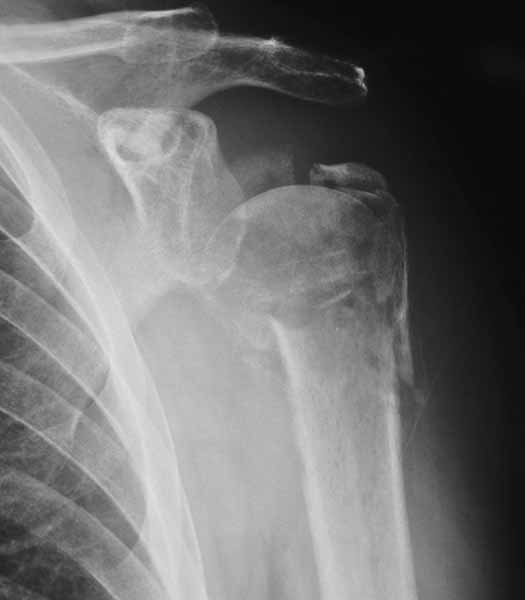

49 yo male RHD architect 3 mos s/p left prox humerus fx/dislocation in MCA presented today wanting know if he had any other treatment options at this time. He had initial PP, which was better reduced, but fell back into valgus impaction. He has 45 degrees FF, 40 degrees Abduction, 20 degrees ER of motion now w/ limited function.

Anyone consider ORIF and use Norian as reported for acute valgus impacted fx in Sept JBJS, Hemiarthroplasty or leave it alone?

I would consider using the Synthes Proximal Humerus Locking Plate through a deltopectoral incision. After disimpacting the head you should be able to get good stabilization even in this very osteoporotic bone with the combination of converging and diverging holes. I would fill in the resulting defect with your bone volume replacement of choice. We still tend to favor autologous bone graft but have also used Norian (the semisolid putty rather than the runny liquid) and other bone graft substitutes. I will try to dig up some intraoperative and clinical photos as well as radiographs.

This was a 23 yo male run over by a boat with multiple propeller injuries. The fixation was carried out after several washouts with good granulation beginning and no evidence of infection. We utilized the one of the lacerations for our modified deltopectoral approach as shown in the first photo. The second photo shows the plate in place, held with a tenaculum forceps. The K-wire fits through the most superior hole in the plate with it's attached template guide. It should skim just superior to the tuberosities across the superior head and is only for positioning the plate. The third photo shows an intraoperative fluoro shot of the plate in position. The K-wire looks to be a little inferior but it may be projection. We have placed a screw through a slotted hole on the shaft to allow proximal and distal correction while maintaining rotational alignment. You can see the drill bit through the tower in one of the proximal locking holes. Sorry these aren't the greatest. I will try to dig up some better shots and some x-rays. I echo the sentiments of others that he is not likely to gain a tremendous amount of motion but we have been surprised on several occasions. From the radiographs you provided it appears that the tuberosities and, therefore, probably the rotator cuff attachments are in the ballpark although you may find it necessary to tack those down with sutures through the plate to restore the integrity of the cuff. Be prepared for the subluxation to persist for quite a while even with stabilization but it will likely improve with therapy if the cuff is attached. I have started these patients on passive, patient controlled ROM on POD #1 with flexion to 90 degrees, abduction to 70-90 degrees, and internal and external rotation to 90 degrees and neutral respectively. I'm encouraged that some recent articles have looked at comparisons between ORIF and hemiarthroplasty for Neer IIIs and IV and shown very similar results. I will send the references as soon as I am able to locate the article in my mountain of journal club articles waiting to be filed. We don't have a large series yet because the plates are relatively new (I think we were a test market) but in the dozen or so we have done we have not had any nonunions and all have had significant improvement in pain. Good luck. Warmest regards,

It's hard to tell from the xrays exactly how thin the head fragment is but I wonder if you were able to get screws right up to the subchondral bone, backfilling the impacted area well with bone graft, and be a little more protective, if you wouldn't be able to get it to heal. I think that a hemiarthroplasty, while certainly a reasonable choice, burns another bridge. Tough case for sure.